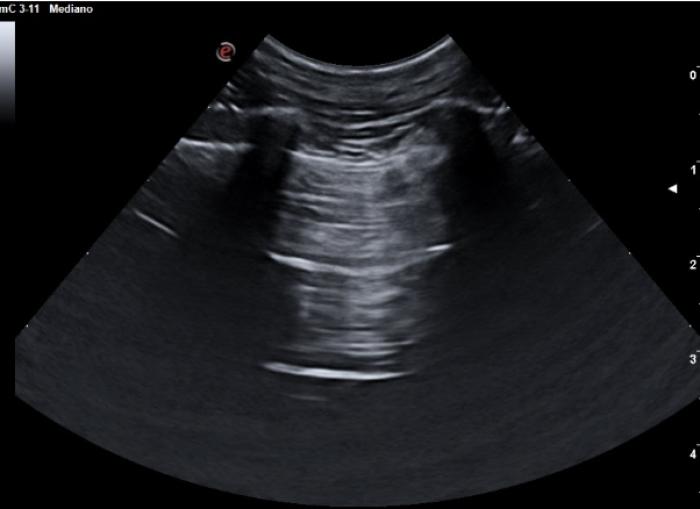

La presencia de pequeñas colecciones de fluido en el espacio pleural no siempre son del todo fáciles de evaluar, especialmente si el contenido en cuestión es lo suficientemente celular como para no visualizarse anecoico. El uso del modo M en estas circunstancias puede ser muy útil. Nos posicionamos con el transductor transversal en el espacio intercostal seleccionado (áreas más declives tienen mayor porcentaje de éxito puesto que el fluido desciende por gravedad), situamos el cursor y activamos el modo M, puesto que el pulmón no está en contacto en todo momento con la pared costal, la LP dibujará un movimiento sinusoidal en el registro en movimiento, muy diferente de la recta hiperecogénica que vemos en el tórax sano (Figura 9A-B).

Por contra, en modo B es posible visualizar lo que se llama signo del cuadrilátero, que es el área comprendida entre la pared costal (límite superior), costillas (laterales) y pleura visceral (límite inferior) dejando un aspecto poligonal en el foco con fluido (Figura 10A-B).